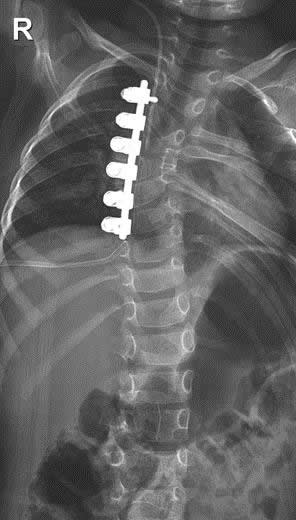

10 Yaş Altı Omurga Deformiteleri

Erken çocukluk (10 yaş altı) dönemindeki omurga deformitelerinin tedavisi farklı prensiplere göre işler. Bu dönemde iskelet sisteminin büyüme potansiyelini bir avantaj olarak kullanmak tedavideki etkin yöntemlerden birisidir. Bu işlem mantık olarak, oluşan eğriliğin dışbükey tarafının fazla büyümesi ya da iç bükey tarafın az büyümesinin dengelenmesi prensibine dayanır. Sonuç olarak da dışbükey tarafın büyümesinin durdurulması hedeflenir. Aşağıdaki olgu beş yaşındadır. Dışbükey tarafın büyümesini durdurmak için ameliyat edilmiştir. İç bükey tarafın zaman içinde az da olsa büyümeye devam edeceği ve zamanla eğriliğin azalacağı ya da en azından ilerlemeyeceği öngörülmüştür. Ancak belirtmem gerekir ki, bu tarz ameliyatların belli şartları vardır ve her olgu için uygun değildir.